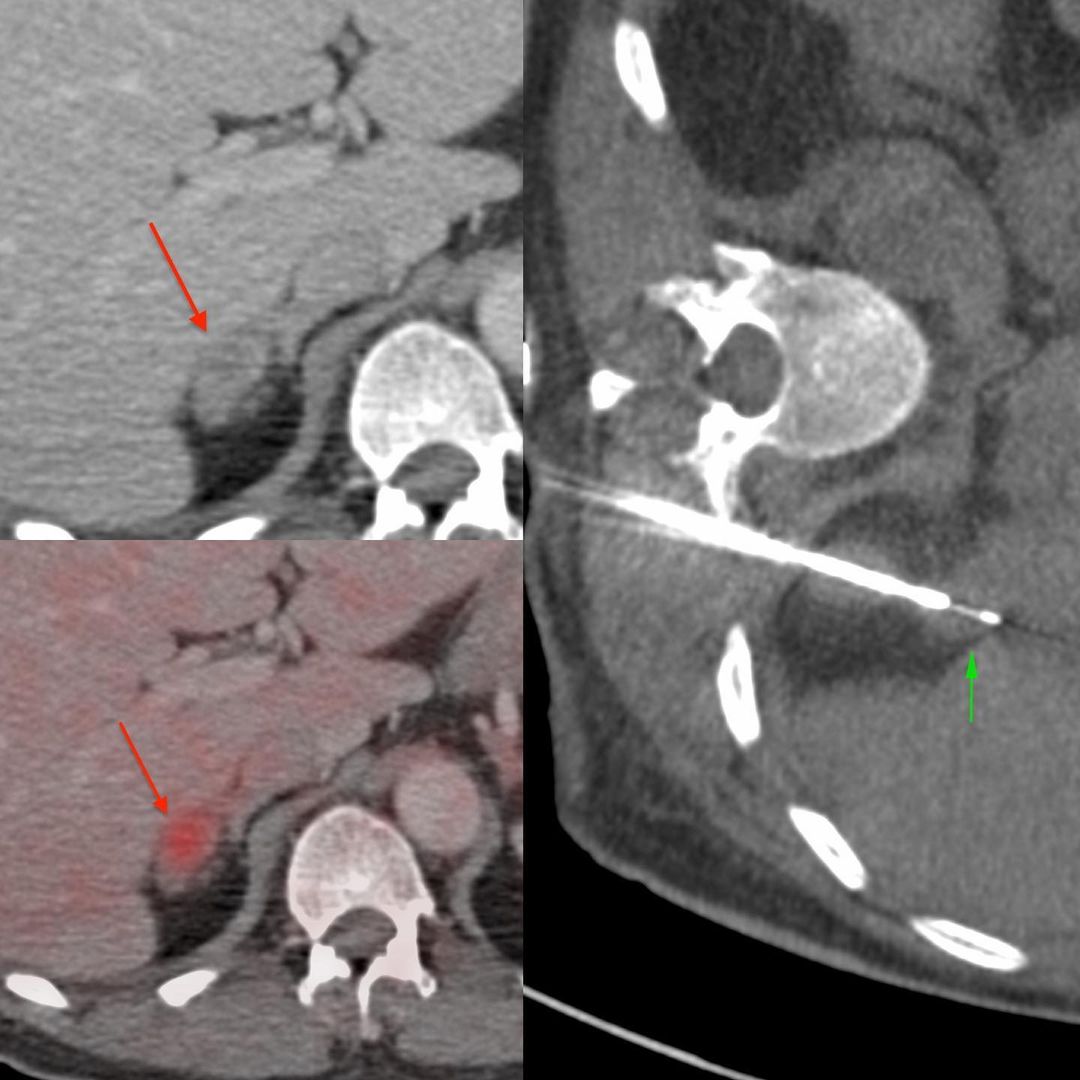

A 70-years old man treated for carcinoma tongue came with a rib mass. The PET/CT also showed a right adrenal nodule and he came for biopsies of both lesions.

The right adrenal nodule measured 14 x 9 mm in diameter. Since the lung and pleura would be in the way, in the prone position, the ipsilateral decubitus position was chosen, which splints the diaphragm and allows good access as well.

As seen here, it was easy to find a path along the para-vertebral region, just superior to the upper pole of the kidney using a 20G coaxial biopsy gun.

The diagnosis was metastasis, consistent with a squamous cell tongue primary.